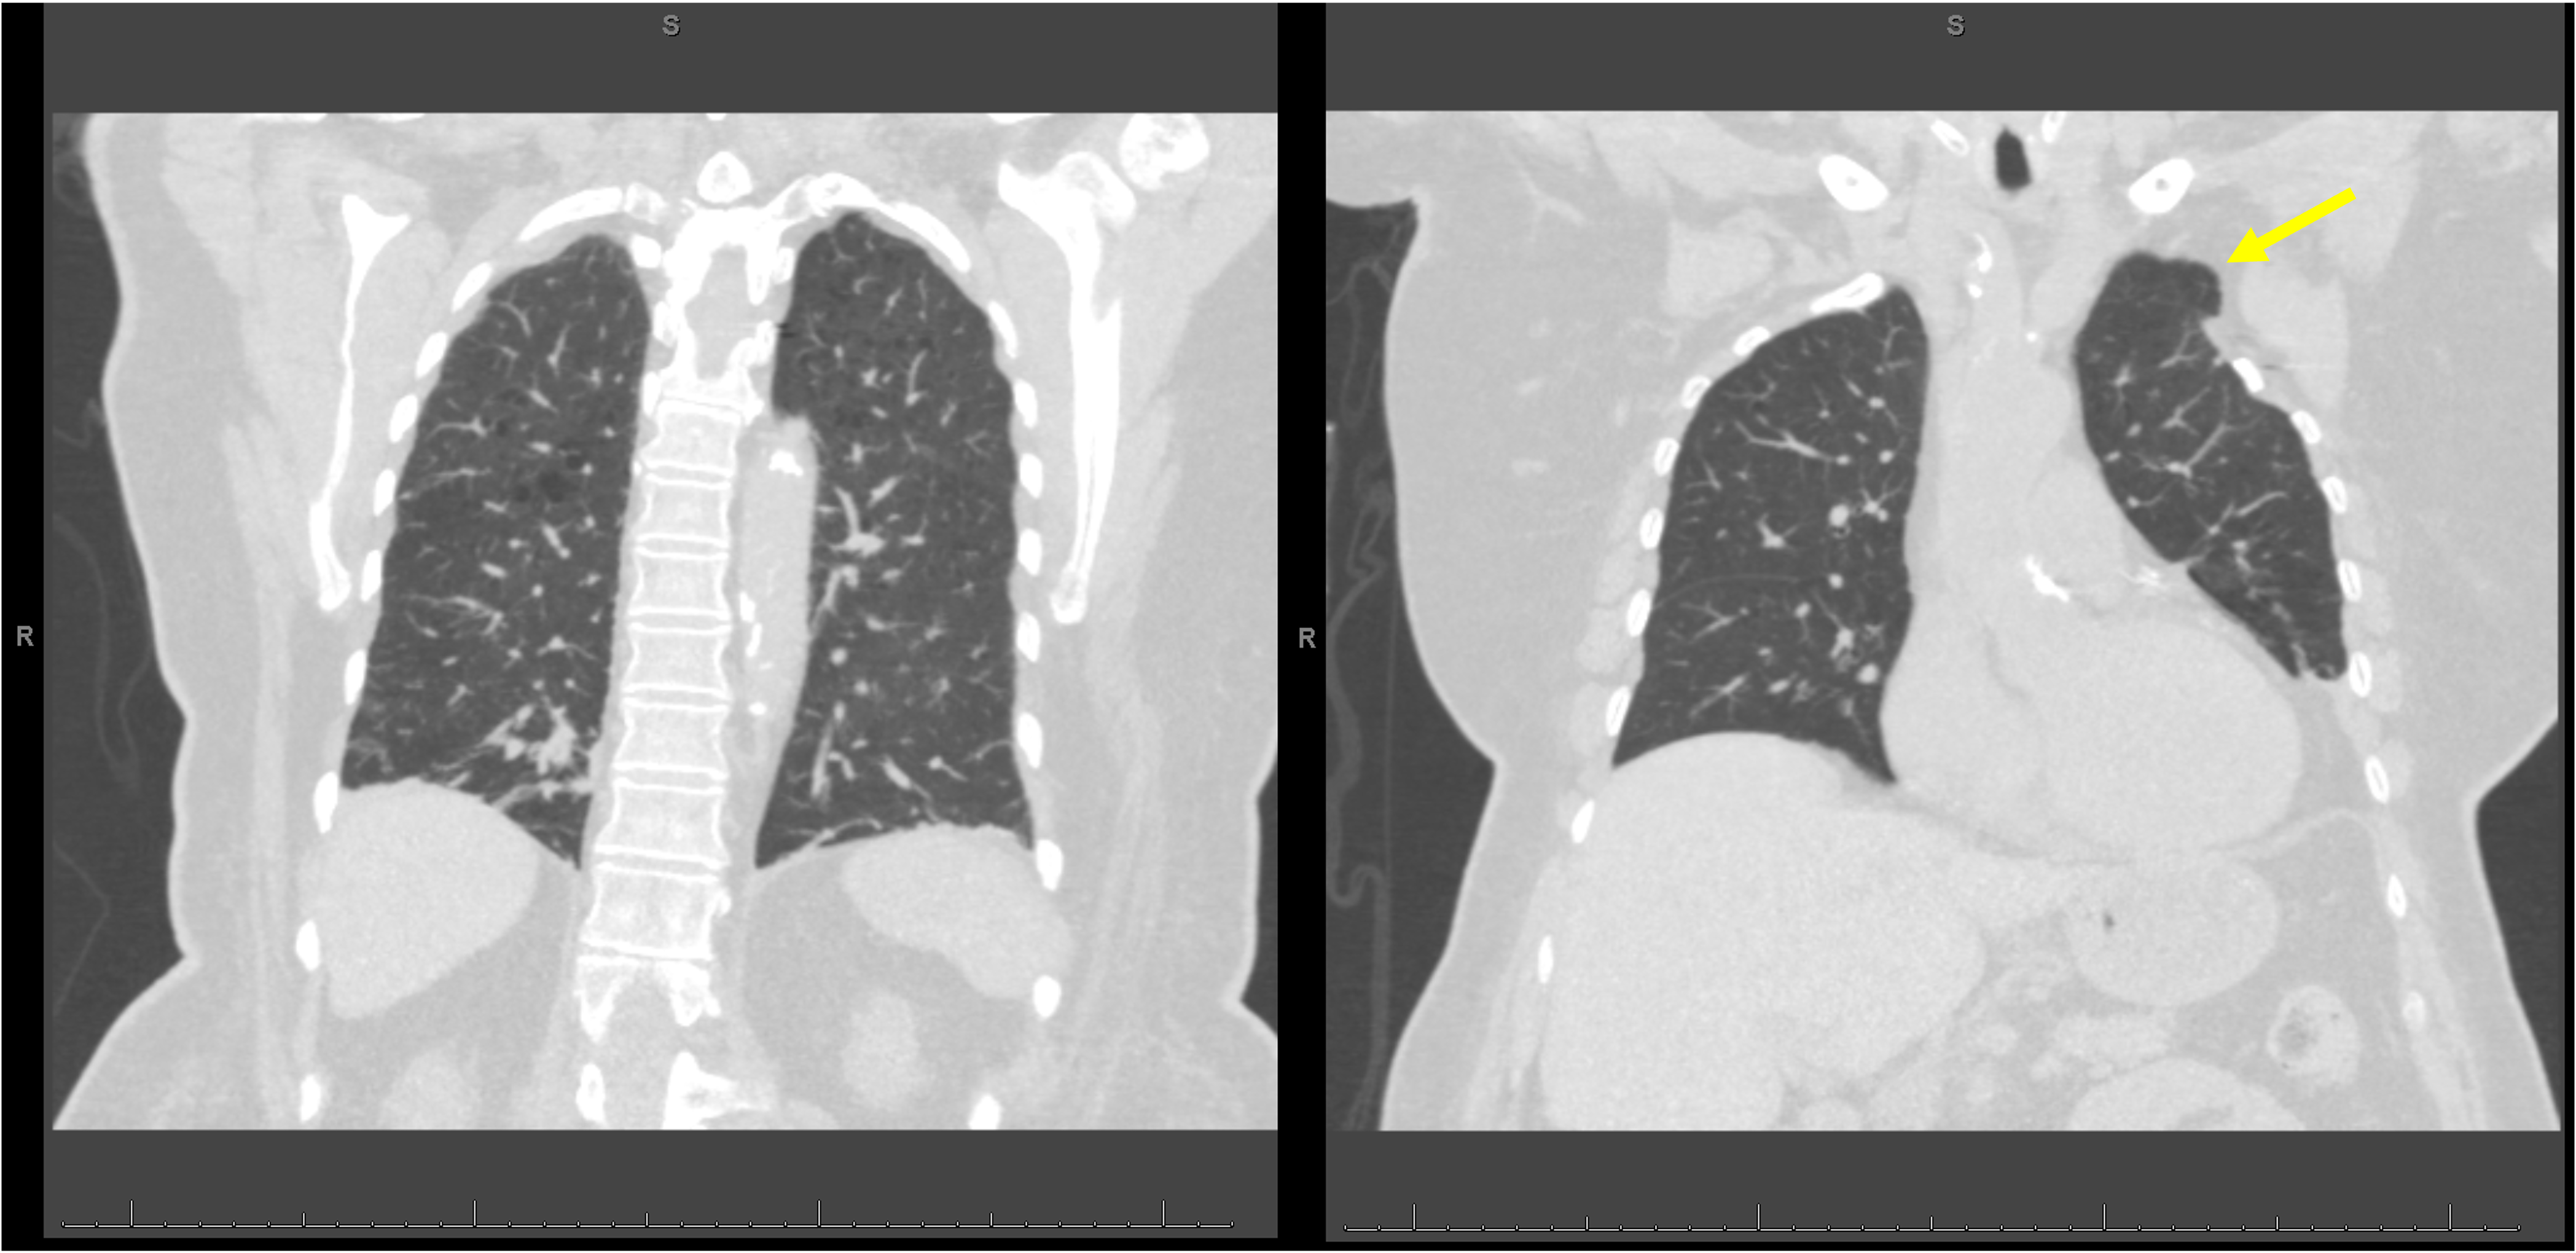

An 83-year-old woman presented to the hospital with dyspnea. She had a history of chronic obstructive pulmonary disease (COPD), obstructive sleep apnea, and thoracic outlet obstruction status post left first rib removal 60 years ago. She also reported lower extremity edema, weight gain, and joint pain. Her vital signs included a heart rate of 68 beats per minute, blood pressure of 186/75 mmHg, respiratory rate of 20 breaths per minute, oxygen saturation was 98% on 2 liters per minute of oxygen, and she was afebrile. The patient’s physical exam was notable for normal respiratory effort, wheezing and crackles on lung exam, and pretibial edema. A plain chest radiograph reported no focal consolidation, edema, effusion, or pneumothorax. Point of care ultrasound (POCUS) of the lungs demonstrated bilateral lung points (Figures 1A and 1B, Supplemental Video S1 and S2) at the left second intercostal space midclavicular line and the right fourth intercostal space anterior axillary line. Scattered B-lines were observed in lung regions outside the focal areas that lacked pleural sliding. A ventilation-perfusion scan was negative for pulmonary embolism. Computed tomography (CT) of the chest was performed to evaluate her dyspnea. It demonstrated emphysematous changes without evidence of pneumothorax, and a small anterior left apical lung hernia at the site of partial left first rib resection (Figure 2). The patient was admitted for a COPD exacerbation.

Figure 2. Computed tomography (CT) chest coronal view with emphysema and no evidence of pneumothorax. The yellow arrow is pointing to the left anterior apical lung herniation at the site of prior surgical first rib removal.